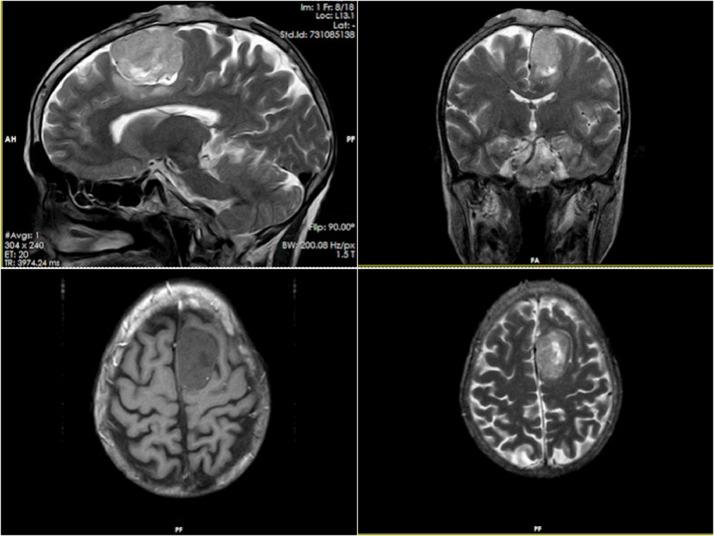

Finding 2 different histological tumor types at the same site is extremely unusual, especially in patients with no history of radiation exposure or a family history of cancer. We describe a rare case of co-occurrence of meningioma and squamous cell carcinoma at the same site. A 67-year-old woman with a 6-month headache and a verrucous ulcerative mass on her frontoparietal region is the subject of this case study. Her medical history and her family's medical history are both blank. Her bilateral frontoparietal regions were found to have large heterogeneous lesions with areas of necrosis and superficial ulceration on radiological examination. An extensive heterogeneous extra-axial lesion was discovered during further radiological analysis in the left parasagittal region. Histopathologic examination revealed an impinging tumor consisting of a meningioma and squamous cell carcinoma at the same site. It is extremely uncommon to have multiple primary scalp cancers of different cell types present at the same time. To identify these cancers and choose the best treatments, clinicians will benefit from the information in our case reports.

在同一部位发现两种不同的组织学肿瘤类型极为罕见,尤其是在没有辐射暴露史或癌症家族史的患者中。我们描述了一例罕见的同一部位同时发生脑膜瘤和鳞状细胞癌的病例。本病例研究的对象是一名67岁女性,她有6个月的头痛史,额顶部有一个疣状溃疡性肿块。她的个人病史和家族病史均无特殊情况。影像学检查发现她的双侧额顶部有巨大的异质性病变,伴有坏死区域和浅表溃疡。在进一步的影像学分析中,在左矢状旁区域发现了一个广泛的异质性轴外病变。组织病理学检查显示在同一部位有一个由脑膜瘤和鳞状细胞癌组成的侵袭性肿瘤。同时出现多种不同细胞类型的原发性头皮癌极为罕见。为了识别这些癌症并选择最佳治疗方案,临床医生将从我们的病例报告中获取的信息中受益。